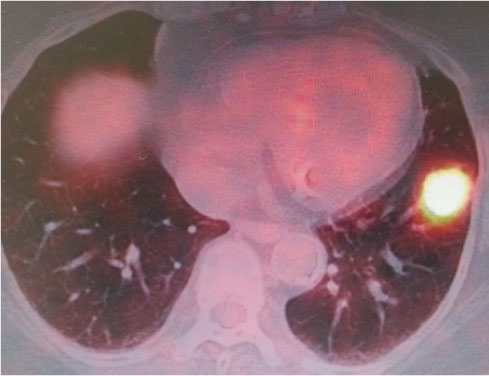

胸部単純CT:左S8肺癌疑い(24mm)

PET:左S8高悪性度肺癌疑い(cT1bN0M0)(SUVmax 7.8→delay 11.6)